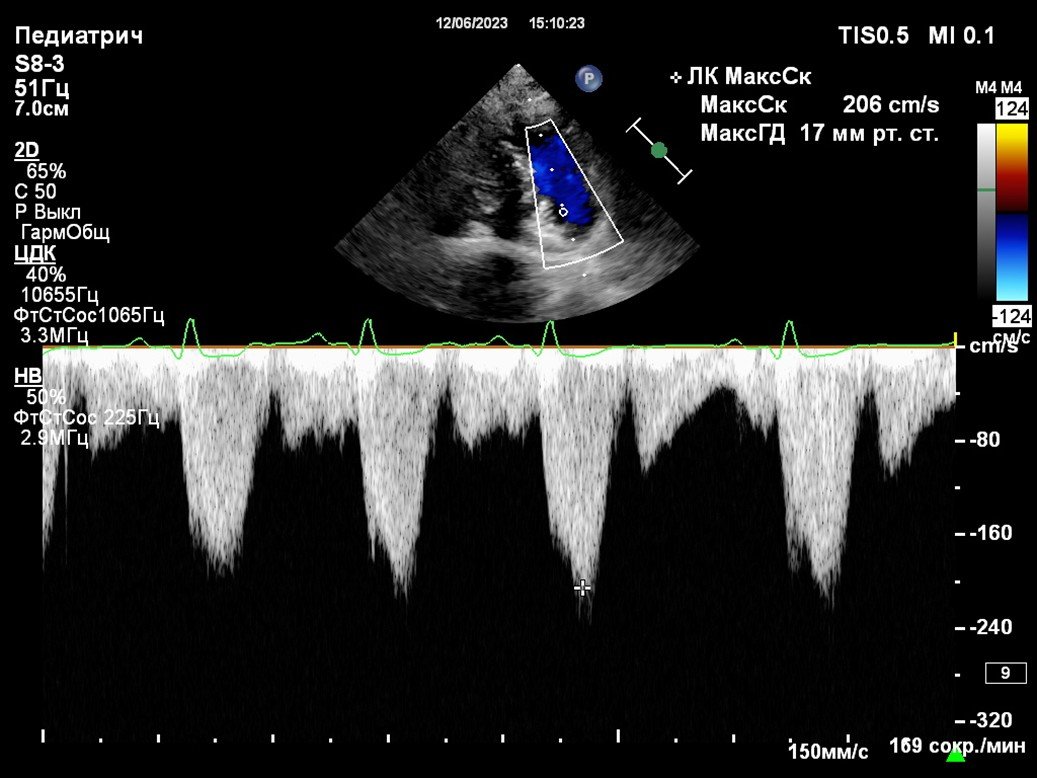

Оценка систолической функции при выявленном шуме

Пациент: Бенни, кокер-спаниель, 7 лет

Жалобы: При плановом осмотре ветеринар выявил систолический шум на верхушке сердца. Собака активна, кашля нет, одышки не отмечается.

Диагноз: Умеренная митральная регургитация, начальная дилатация левого предсердия (LA/Ao = 1.7), фракция выброса — 68%. Диагноз: хроническая митральная недостаточность, стадия B2 по ACVIM.

Что дало ЭХО: ЭХО позволило точно оценить степень клапанной недостаточности, размеры камер и насосную функцию сердца. Это стало основанием для начала профилактической терапии до появления клинических симптомов.

Результат: Назначен ингибитор АПФ и диета с ограничением натрия. Через 6 месяцев — стабильное состояние, прогрессирования нет.